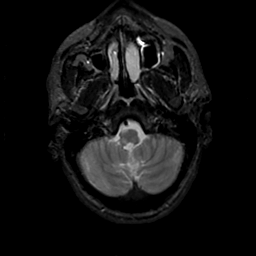

MR Study #18, July 21, 1991 -- Slice #7